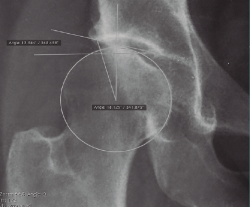

Radiológicamente, estos pacientes en los que podría considerarse un manejo artroscópico se engloban en la displasia de tipo A de Hartofilakidis. Debemos realizar radiología simple anteroposterior de pelvis, axial de Dunn, lateral pura y la proyección de falso perfil de Lequesne. Los ángulos a evaluar serían, de forma básica, el ángulo de inclinación acetabular (IA) o de Tönnis, así como el ángulo centro-borde lateral (CBL) o de Wiberg (Figura 5). En general, el ángulo de IA debe ser menor de 10°, mientras que el ángulo CBL debe ser mayor de 25°.

Figura 5. Medición de los ángulos centro-borde lateral, de 18,1° (Wiberg), y de inclinación acetabular, de 13,5° (Tönnis).